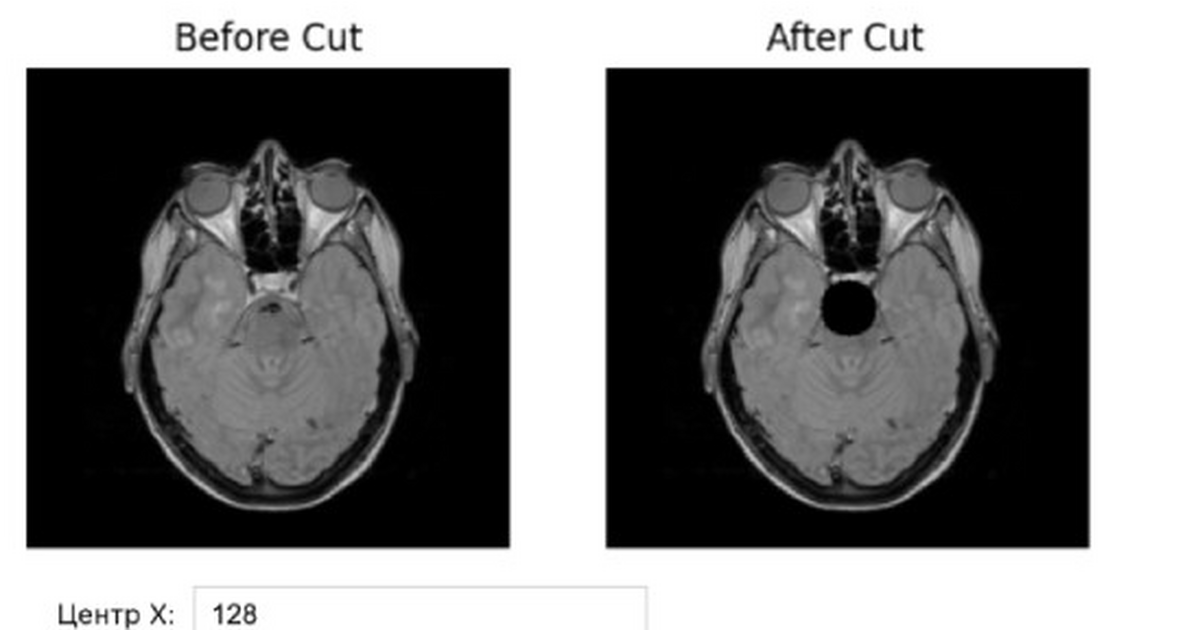

«ДатаСкульпт» решает эту проблему, генерируя синтетические МРТ-снимки с заданной локализацией и выраженностью патологий. Платформа сочетает генерацию изображений с автоматической проверкой их качества, что делает данные безопасными и пригодными для обучения и тестирования ИИ-моделей.